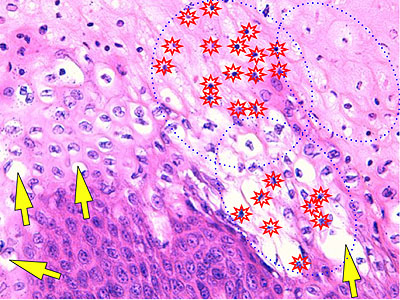

Photo 7 (Hémalun Eosine X 400) : l’aspect blanc donné par les lésions de dégénérescence balonnisante

(œdème cellulaire sévère) des acanthocytes des couches épineuse et granuleuse, qui peut être associée

multifocalement à une pycnose nucléaire (mort cellulaire) aboutissant à un aspect nécrolytique.

Légendes de la Photo 7 :

- Étoiles rouges claires : noyaux pycnotiques (acanthocytes) zones de nécrolyse épidermique

- Flèches jaune : œdème cellulaire ou dégénérescence ballonisante des acanthocytes

Photo 14 (Hémalun Eosine X 400) : vue rapprochée de la fig 13, les lésions d’hyperplasie épidermique,

avec émission de crêtes épithéliales ramifiées, prédominent largement le tableau histologique.

On notera l’aspect très focal et subtil des lésions de dégénérescence balonnisante

d’un groupe de quatre acanthocytes inclus dans la couche cornée.

Légendes de la Photo 14 :

- Triangles bleus clairs : contours de crêtes épithéliales allongées, filiformes, ramifiées et branchues, peuplées de cellules basales hyperbasophiles un petit foyer de 4 acanthocytes ballonisés